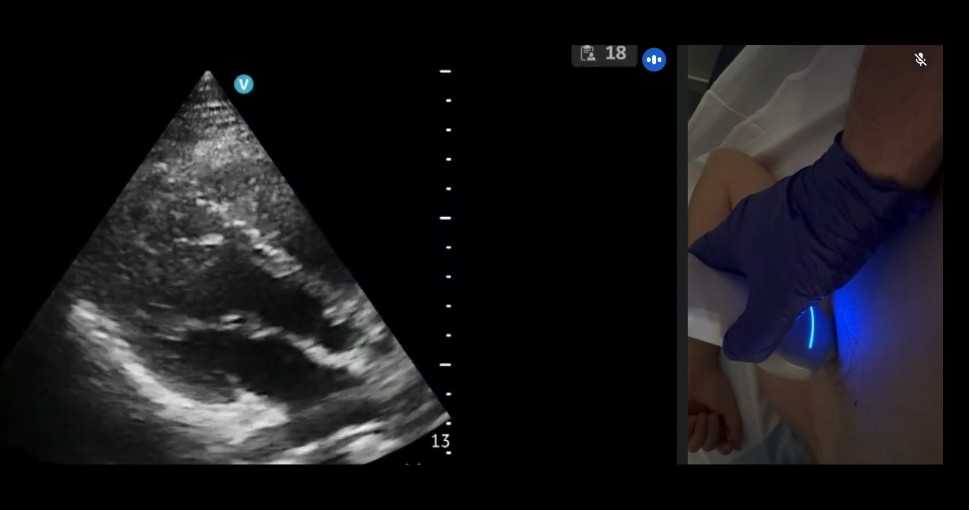

RECURSOS DIDÁCTICOS Inicio » RECURSOS DIDÁCTICOS Videos Documentos Publicaciones Casos clínicos VIDEOS Ver más DOCUMENTOS Checklist muerte encefálica Protocolos de diagnóstico y certificación de la muerte encefálica VSCAN-STROKE: evaluación ultrasonográfica con VSCAN de fuentes embolígenas cardioaórticas por un neurólogo en la fase hiperaguda del ictus isquémico Recomendaciones SONES para realizar estudios ecográficos durante la pandemia SARS-CoV-2 (COVID-19) Impacto de la pandemia covid19 en los laboratorios de neurosonologia Ver más PUBLICACIONES Estado de la neurosonología en España. Un estudio de la Sociedad Española de Neurosonología (SONES). J. Rodríguez-Pardo , J. Carneado-Ruiz, M. Martínez-Martínez, J.M. Moltó-Jordá, P. Irimia, J. Serena-Leal, Ó. Ayo-Martín, P. Martínez Sánchez, J. Pagola J. Fernández-Domínguez Supraesternal aortic debería salir del modo siguiente: Suprasternal aortic arch echocardioscopy as a potential tool in detection and follow-up of mobile thrombi in patients with ischemic stroke. Esnaola Barriola I, Escriche Gorospe E, Miguel Navas P, Martínez Campos E, Molina Goicoechea M, Capell Pascual F, Jiménez Delgado A and Muñoz Arrondo R (2025) Documento de consenso sobre técnicas neurosonológicas en cefaleas. J. Rodríguez Vico, J. Fernández Domínguez, F.J. Julián Villaverde, N. González García, C. García-Cabo Fernández, A. Jaimes Sanchez, O. Ayo Martín, J.A. Membrilla López, R.G. Martínez Martín, J. García Ull, P. Martínez Sánchez, L. Dorado Bouix, R. Belvis Nieto, P. Irimia.Neurología, 2024. Point-of-care ultrasound for transient ischemic attack assessment in transient ischemic attack clinics: Consensus document of the Spanish Society of Neurosonology. Amaya-Pascasio, L., Rodríguez-Pardo de Donlebún, J., Arjona-Padillo, A., Fernández-Domínguez, J., Martínez-Martínez, M., Muñoz-Arrondo, R., García-Sánchez, J. M., Pagola Pérez de la Blanca, J., Carneado-Ruiz, J., & Martínez-Sánchez, P. Neurología. 2024 Increased vertebral canal diameter measured by ultrasonography as a sign of vasculitis in patients with giant cell arteritis. Ayo-Martín O, Segura T et al. Frontiers in Medicine 2023 Transcranial sonography in atypical parkinsonism: how reliable is it in real clinical practice? A multicentre comprehensive study. Alonso Cánovas A, Tembl Ferrairó JI, Martínez-Torres I, López-Sendón Moreno JL, Paree-Moreno I, Monreal-Laguillo E et al. Parkinsonism related disorders 2019; 68: 40-45 Qué debería saber el médico de familia sobre la ecografía transcraneal en neurología. Fernández Domínguez J. FMC 2016; 23 (8): 467-473 Evaluación de la sustancia negra mediante ultrasonografía transcraneal. Vivó-Orti M, Tembl JI, Sastre-Bataller I, Vázquez-Costa JF, Sahuquillo P, Burguera JA. Rev Neurol 2013; 56 (5): 268-274 Utilidad del duplex orbitario para la valoración de atrofia del nervio óptico en enfermedades desmielinizantes: estudio piloto. Fernández-Domínguez J, García-Rodríguez R, Mateos V. Rev Neurol 2012; 54 (10): 587-592 Dúplex transcraneal en la enfermedad de moyamoya. Vázquez-Sánchez F, López-Veloso M, Argandoña-Palacios L, Segura T. Rev Neurol 2012; 54 (2): 249-250 Ver más CASOS CLÍNICOS Caso 7 – 2023 Ver caso Ver todos los casos SONES SOCIEDAD ESPAÑOLADE NEUROSONOLOGÍA secretariasones@gmail.com HAZTE SOCIO ¡Síguenos en Twitter!